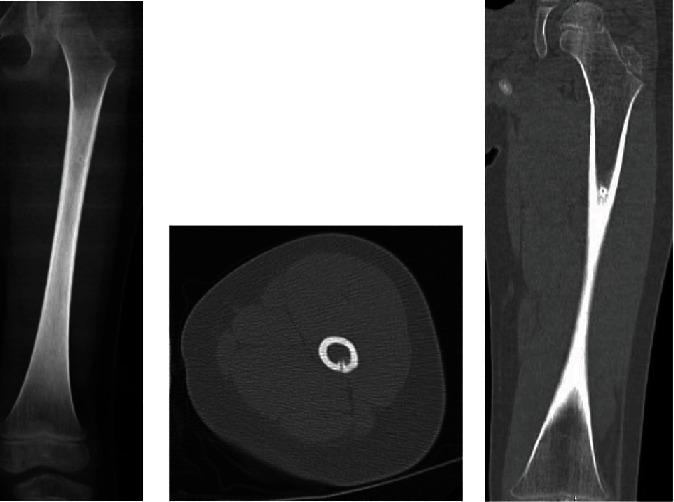

This is a case report of a 4-year-old girl who sustained a femoral shaft fracture 2 weeks after radiofrequency ablation of an osteoid osteoma. The fracture occurred after a relatively low-energy impact, jumping off the second to last step of a staircase. The pathologic fracture was successfully treated with closed reduction and spica casting, with full return to activities. Cases have been reported in the literature of femoral shaft fractures in older patients after radiofrequency ablation, but all are farther out than 2 weeks and none in patients as young as 4 years.

这是一例4岁女童的病例报告,该女童在骨样骨瘤射频消融术后2周发生股骨干骨折。骨折发生在相对低能量冲击后,从楼梯倒数第二步跳下时。该病理性骨折通过闭合复位和髋人字石膏固定成功治疗,患儿完全恢复活动。文献中已有关于老年患者射频消融术后股骨干骨折的报道,但时间均超过2周,且无4岁这么小年龄患者的相关报道。